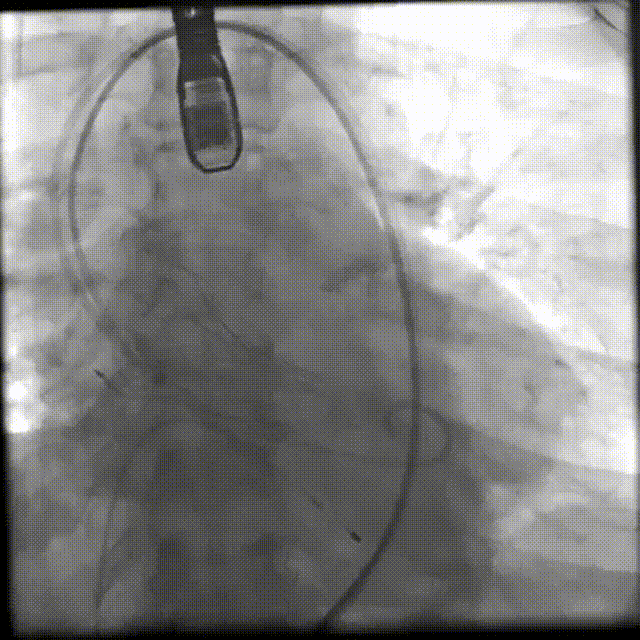

5.根据术前评估及球囊预扩情况,选择23mm沛嘉TaurusElite瓣膜进行植入,在140次/分保护起搏下0位释放瓣膜,一次释放到位。

6.造影评估示瓣膜植入深度、工作形态良好、微量瓣周漏,交换猪尾导管测的平均跨瓣压差22mmHg,手术圆满成功。

通过术前缜密分析,秦永文教授带领手术团队制作了周密的手术预案,并初步决定以18mm球囊进行预扩,以23mm沛嘉TaurusElite瓣膜植入,为之后手术的顺利开展打下坚实基础。手术当日,秦永文教授、白元副教授及许旭东副教授等专家通力合作,顺利完成手术。依照既定策略选用18mm TaurusAtlas球囊预扩后,造影未见明显腰征,瓣环平面未见球囊压缩,可见微量造影剂渗漏,明确了23mm TaurusElite瓣膜的选择。瓣膜过弓过程相当顺利,TaurusElite输送器良好的通过性能,有效降低了血管并发症的发生风险。

在瓣膜释放环节,TaurusElite大手柄具有的良好操作性,帮助术者进行了精确的释放定位。基于术者娴熟的操作,瓣膜一次性定位释放成功。释放完成后,即时超声评估提示微量瓣周漏,跨瓣压差稳定在22mmHg,符合术前预期,宣告手术成功完成。